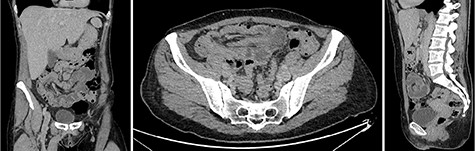

The patient was urgently taken to the operating room with a pre-operative diagnosis of colon intussusception and underwent laparoscopy. Intra-operatively, colocolic intussusception was present. The cecum was found to be the intussusceptum, subsequently telescoping far into the transverse colon that was found to be the intussuscipiens (Fig. 3).

Intra-operative finding of the intussusception. (Left) The terminal ileum and the appendix were pulled like a tail by the intussusceptum into the intussusception. (Right) The cecum was identified as the intussusceptum, telescoping into the transverse colon that was identified as the intussuscipiens.